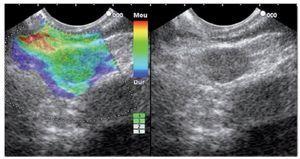

Category 1 is for a homogenous low elastography area (soft, green) and corresponds to the normal pancreas tissue (Figure 1). For images classified as category 2 (Figure 2) there is heterogeneity of the elastography but in the soft tissue range (green, yellow, and red) and corresponds to fibrosis. Category 3 (Figure 3) is for elastography images which is largely blue (hard) with minimal heterogeneity and corresponds to a small, early (less than 25 mm) pancreatic adenocarcinoma. In tumors assigned Category 4 (Figure 4) there exists an hypoechoic region with green appearance in the center of the tumor, surrounded by blue or harder tissue and corresponds to a hypervascular lesion, such as a neuroendocrine tumor or small pancreatic metastasis. Finally, Category 5 (Figure 5) is assigned to lesions which are largely blue on SE but with heterogeneity of softer tissue colors (green, red), representing necrosis, and is seen in advanced pancreatic adenocarcinoma. The elasticity of soft tissues depends to a large extent on their molecular composition (fat, collagen, etc.), as well as on the microscopic and macroscopic structural organization of these blocks. In the normal pancreas, for example, the glandular structure may be firmer than the surrounding connective tissue, which in turn is firmer than the subcutaneous fat. SE allows the hardness or stiffness of biological tissues to be estimated and imaged using conventional ultrasound instruments with modified software. It is known that certain pathologic conditions, such as malignant tumors, often manifest themselves as changes in the mechanical properties of tissue. We believe that the elastic properties of benign lesions are fairly uniform, such as throughout a benign tumor. Cancerous tumors, on the other hand, grow in a very disorganized way. Therefore, within a given malignant tumor, the elastic properties of one area of a tumor may be significantly different from those in another area. The concept relating to the measurement of these tissue changes is an extension of the basic principles associated with traditional medical ultrasonic imaging. The principle is based upon the fact that tissues are deformed slightly when a small displacement is externally applied

Figure 5. Category 5, lesions which are largely blue but are heterogeneous with softer tissue colors (green, red), representing necrosis; usually seen in advanced pancreatic adenocarcinoma.